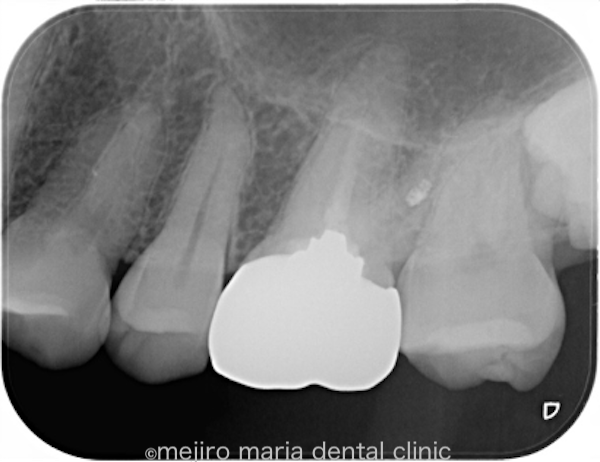

左上6番(上顎左側第2大臼歯)は既に根管治療が施されており、根尖性歯周炎は根尖に確認されないものの、以前の治療の質は良い状態ではない(質が低い)ことが予想できます。根管治療の質を高める意味合いで再根管治療をご提案させていただきました。